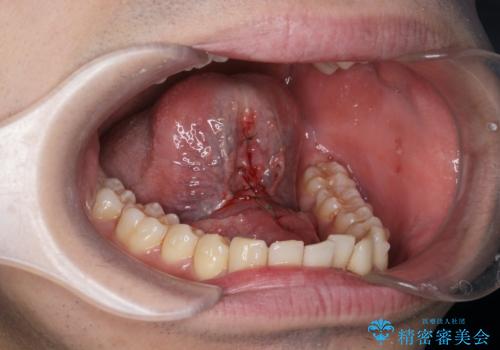

滑舌の改善 舌小帯の形成術

- 舌が動かしづらく、滑舌の改善を希望され来院されました。

舌小帯の形成術を即日で行い、1週間後に抜糸を行います。滑舌の改善を実感され、喜んでいただくことができました.

舌小帯の形成術は約10分程度で終了する小手術です。